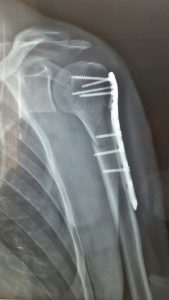

Fractura de Húmero proximal julio 17, 2017 por admin Fractura de húmero proximal, osteosíntesis con placa y tornillos.